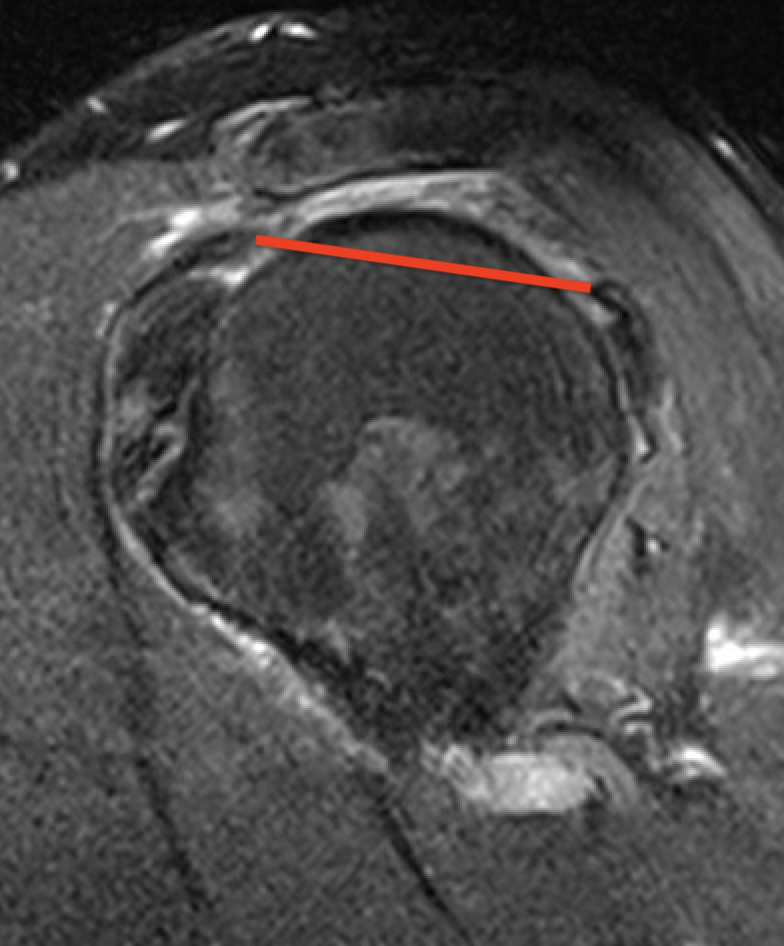

Supraspinatus atrophy

Tangent sign

- sagittal MRI

- line connecting superior coracoid and superior border scapular spine

- if supraspinatus muscle is below line, there is significant atrophy

- positive tangent sign / significant atrophy associated with larger tears / irrepairable tears

Negative tangent / no atrophy Positive tangent / significant supraspinatus atrophy